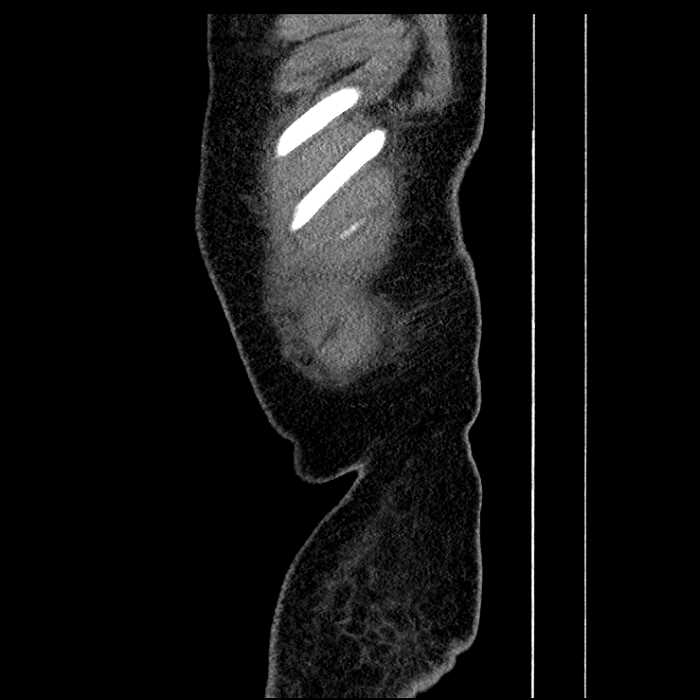

• Mild mural thickening of a segment of the sigmoid colon with adjacent fat stranding and a 1.5 cm fluid and gas collection along the tip of an inflamed diverticulum

• Loss of the normal fat plane between this collection and adjacent loops of small bowel, which demonstrate mural thickening

Acute sigmoid diverticulitis complicated by a small contained perforation and a large abscess in the right hepatic lobe. Additional small subcapsular abscesses along the anterior margin of the left hepatic lobe.

Additionally, loss of the normal fat plane between the peridiverticular collection and adjacent thickened loops of small bowel raises the potential for an enterocolonic fistula.

Hepatic abscess showing the double target sign with low density internally surrounded by a thin inner enhancing rim (red arrow) and ill-defined outer low density rim (yellow arrow). Blue arrow indicates an internal septation. Red arrows: additional smaller subcapsular abscesses. Red arrow: focal contained perforation associated with diverticulitis.